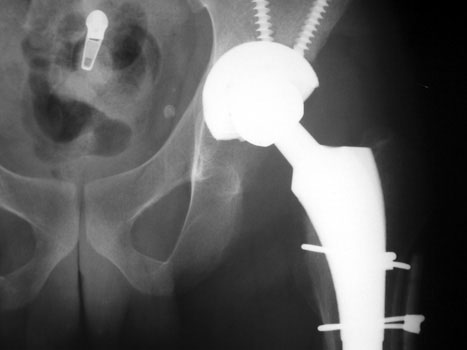

Resection of hardware, cement spacer placement

Cement spacers are antibiotic impregnated, allowing for local dispersal of antibiotics.

• Maintain leg length

• Minimize dead space

• Preserve soft tissue planes

• Facilitate ease of revision arthroplasty

Cement spacers are fabricated in the surgical suite using methylmethacralate cement impregnated with antibiotics sensitive to cultured organisms. A Rush rod is cut and bent to 120 degrees to mimic the femoral neck-shaft angle. Antibiotic impregnated cement is placed into a blue bulb syringe which simulates the femoral head contour and allowed to dry. The plastic is then removed. A second batch of cement is prepared and formed around the femoral shaft portion of the Rush rod.